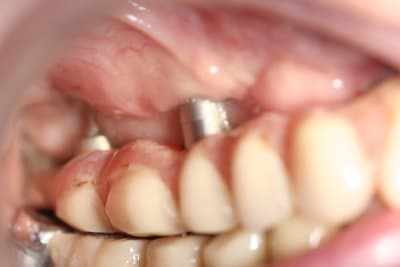

Ben il est où le problème ?

Sur cette radio, on voit pas grand chose...

Ça bouge ?

il y a des péri-implantites sur quasi tout les disk du haut, c'est cà?

En pratique, c'est quoi le problème avec les disk ? On voit pas bien sur la pano periimplantite ? sinon il va y avoir besoin d'encore un peu de titane en secteur 4

Non, ce n'est pas un problème de tourne disque mais plutôt de peri-implantite dans le secteur antérieur.

Effectivement, pas de mobilité.